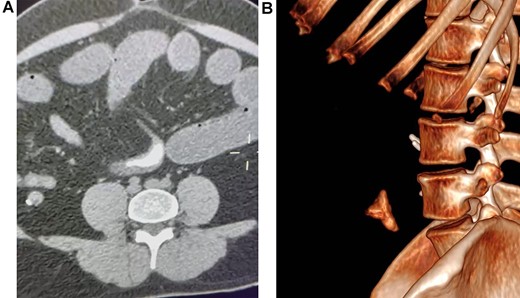

The abdominal CT revealed severe distention of small bowel loops, compatible with intestinal obstruction, and a hyperdense 4 x 3 cm foreign body in the lumen of the jejunum. Surgical consultation was needed, and with these findings, surgery was planned (Fig. 1A and 1B).

(A) Abdominal CT, revealing a foreign body in the lumen of the bowel. (B) CT reconstruction of the foreign body.